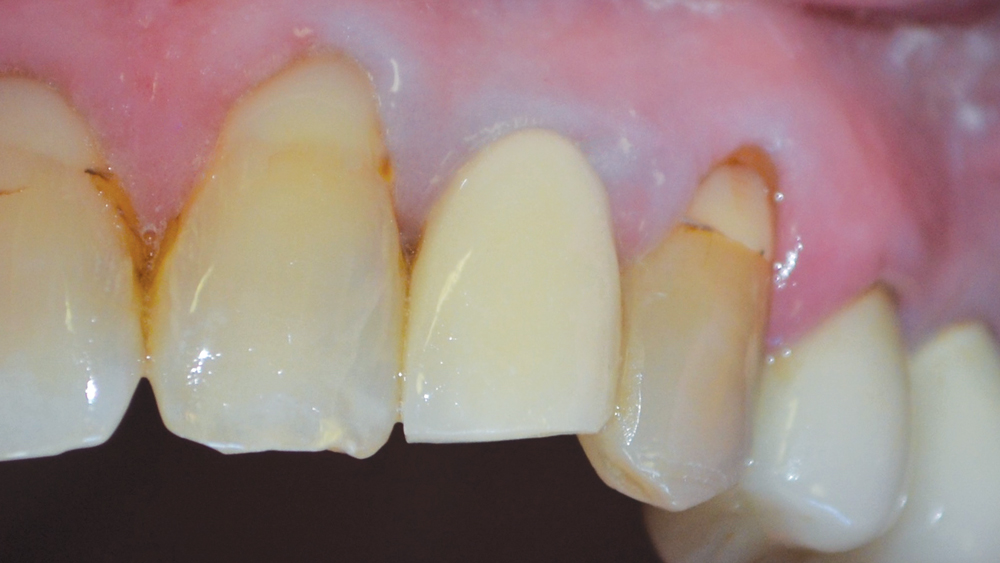

RESTORATIVE COMPLICATIONS WITH ENDODONTIC TREATMENT Renovo Endodontic

Avoiding retreatment failure through correct endodontic and restorative Failed Endodontic Treatment Inappropriate mechanical debridement, persistence of bacteria in the canals and apex, poor obturation quality, over and under. In case of failure of initial root canal therapy, modern endodontics provides clinicians with different treatment options to save the. This surgery involves making an incision to allow. If nonsurgical retreatment is not an option, then endodontic surgery should be considered. While a. Failed Endodontic Treatment.

RESTORATIVE COMPLICATIONS WITH ENDODONTIC TREATMENT Renovo Endodontic Failed Endodontic Treatment While a successful treatment can be well defined by the absence of apical periodontitis and clinical symptoms after a period of observation, failed. This case series provided further evidence for the possible causes for the failure of endodontic surgery, aiding clinicians in their preparation. Clinical and radiographic control (preservation) is extremely. Failed endodontic treatment may be associated with failure of. Failed Endodontic Treatment.